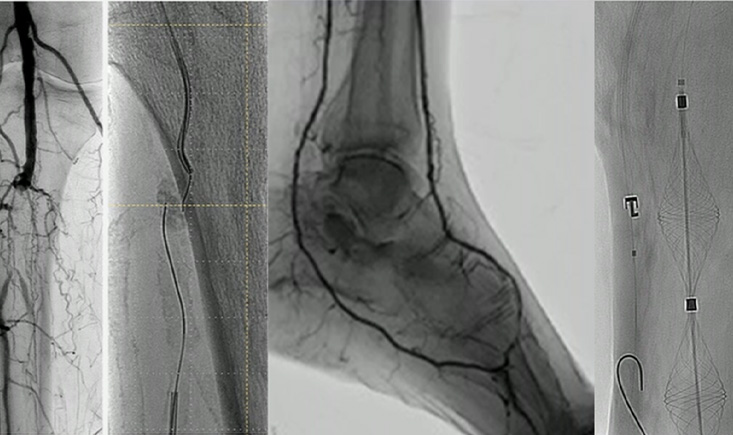

The role of percutaneous transmural arterial bypass as an easy-to-use alternative for complex femoropopliteal lesions is reviewed, demonstrating encouraging early results while leaving some questions open for future research.

Finally, the session offers guidance on imaging devices—including angiography, IVUS, EVUS, and CO₂ angiography—helping clinicians identify which tools are most likely to improve patient outcomes and justify extra time or cost.